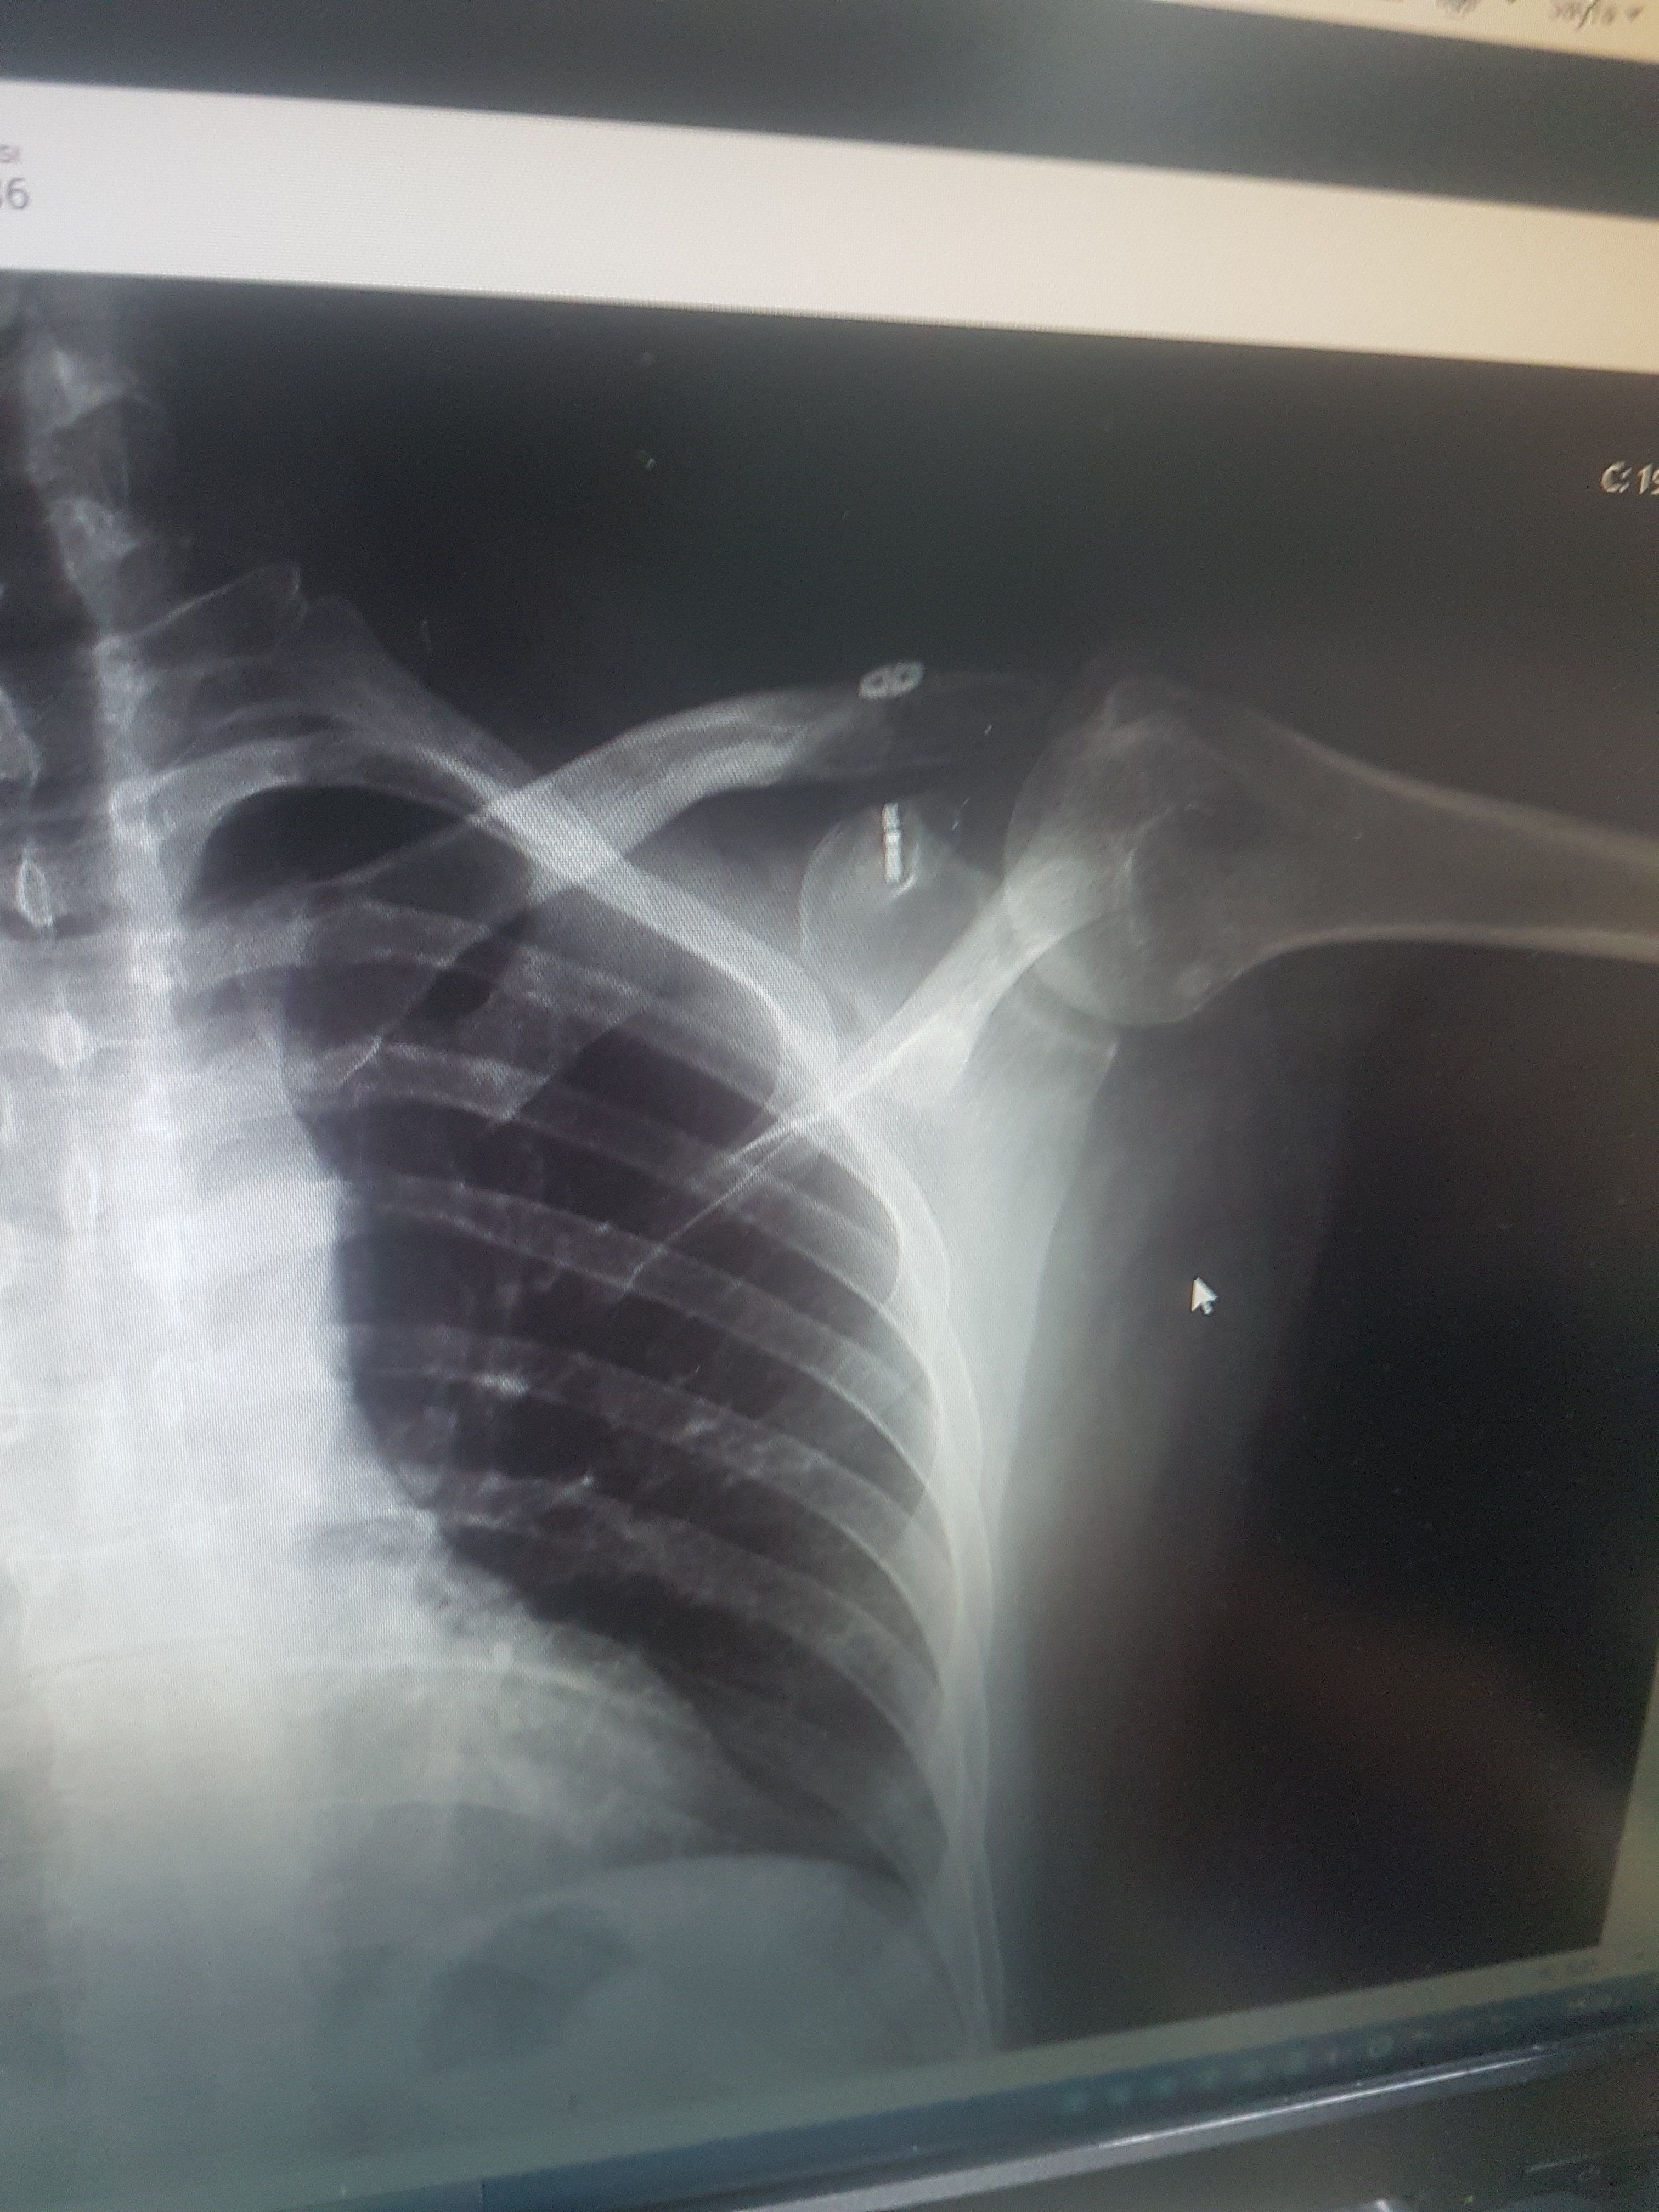

@caglar14 Aynı ameliyatı oldum 3. ay sonunda ip koptu. Çok sinirim bozuldu. Şimdi kemik yukarıda duruyor. Sadece benim mi başıma geliyor derken demek ki olabiliyormuş. Bir prof bana sağlam malzeme kullanmama kaynaklı demişti. Anlattığına göre ton kaldıran ip nasıl kopar mış ? Ya iyi tutturamadılar yada malzeme kötü dedi. Arada bir daha operasyon yaptırsam mı diyorum ama alıştım da. Siz bıraktınız mı öyle.